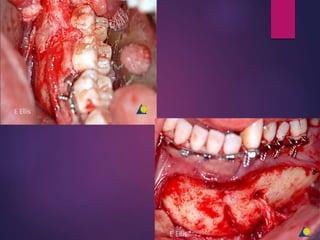

• #30 The fracture was debrided, the plate removed, the infection drained, and the patient placed on antibiotics to control infection. Once infection has subsided, the patient was taken to surgery and the fracture exposed through a submandibular approach. The fibrous tissue between the fragments was debrided and the fragments decorticated.

• #31 The occlusion was reestablished with MMF. A reconstruction plate was then adapted and secured to provide load-bearing fixation across the fracture gap.. Particulate autogenous bone was placed into the fracture gap and the incision closed in layers.

• #39 Intraoperative photograph showing malunion of left parasymphyseal fracture. Rt angle region

• #40 angle osteotomy and fixation with two miniplates.